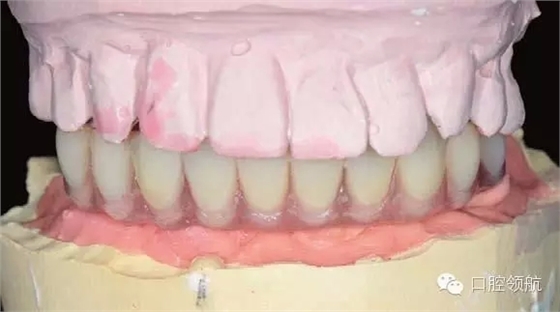

手術(shù)當(dāng)天取模,當(dāng)天灌注石膏模型,上牙合架,開始準(zhǔn)備制作螺絲固定的過渡義齒(圖6-11,圖6-12)。

技師手術(shù)當(dāng)天在門診配合,制作的螺絲固位過渡義齒。制作方法為自凝基托材料固定的人工牙。連同石膏模型的灌注到制作完成,需要3~4小時。過渡義齒制作的時間越短,術(shù)后戴牙越快越有利于控制患者的術(shù)后反應(yīng):減少術(shù)后的傷口滲血、減少軟組織的腫脹等。

圖6-13和圖6-14分別為牙合架上的塑料過渡義齒。因為考慮縮短制作的時間,因此All-o n-4的術(shù)后螺絲固位過渡義齒使用自凝材料,同時用硅橡膠包埋蠟牙法制作。

圖6-13 排牙結(jié)束后的正面照片

同時因為是即刻負(fù)重,為了減少不必要的風(fēng)險,通常不制作遠(yuǎn)中的游離端,該病例即刻負(fù)重過渡義齒修復(fù)到兩側(cè)的第二前磨牙,待永久修復(fù)時再增加兩側(cè)的第一磨牙。